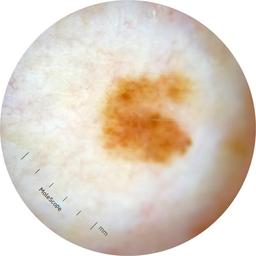

ISIC_6708537

Information

2077 x 2077

Clinical

Field Value

acquisition_day 525

age_approx 70

anatom_site_1 Upper extremity

anatom_site_general upper extremity

concomitant_biopsy False

diagnosis_1 Benign

diagnosis_confirm_type single image expert consensus

family_hx_mm False

fitzpatrick_skin_type I

image_manipulation instrument only

image_type dermoscopic

lesion_id IL_6558300

patient_id IP_3297880

personal_hx_mm True

sex female